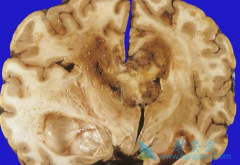

阿瓦斯汀( 贝伐单抗 )是治疗进展期胶质母细胞瘤(GBM)的重要手段之一,是在2009年被美国FDA批准治疗此病的药物。根据多项临床研究,阿瓦斯汀推荐的有效剂量为5mg/kg/周,并沿用至今。众所周知,过高的剂量可能会激活利于肿瘤生长的信号通路,并带来更 ...

肿瘤脑转移治疗难度较大,生活质量较差,在脑转移后期,多数患者会发生剧烈头痛、抽搐、呕吐、视力障甚至精神异常等症状。目前,脑转移治疗方式较为有限,主要治疗手段是局部放疗(如伽马刀),对部分患者能起到一定作用。但近年来逐渐热门的免疫治疗, ...